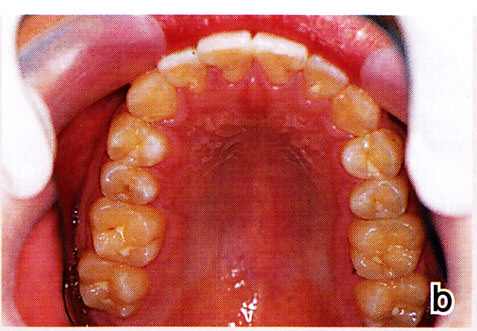

図15 a~c:18歳 下顎前歯に少し乱れが出ているが、臼歯のアップライトが不十分なためと思われる